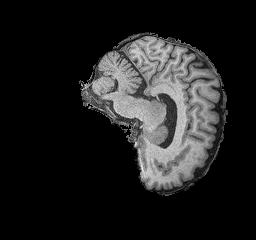

Figure 3: NC brain example